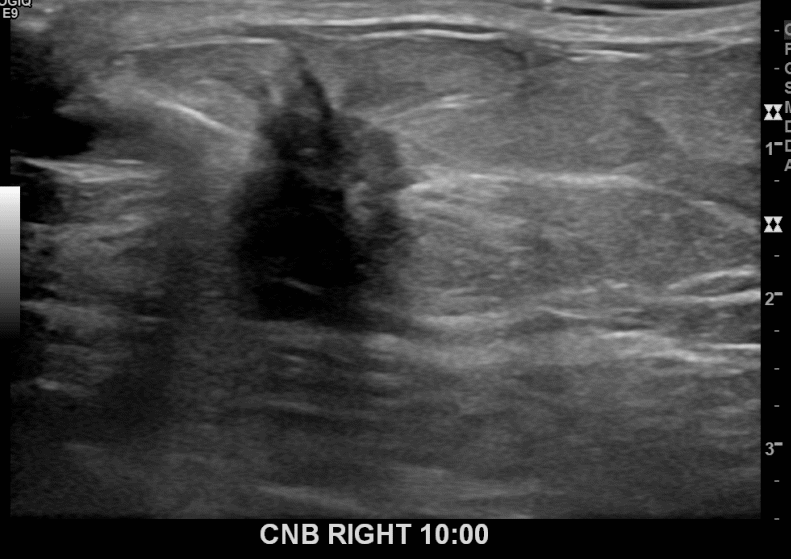

아산유외과개원후 678번째 유방암진단

상기환자 외부검사상 이상소견으로 내원하신 60대여성으로 우측에 의심스러운혹 조직검사시행해 유방암 진단되었습니다.